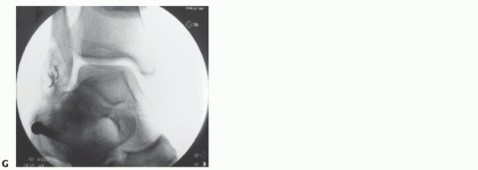

FIG 1 • A. Plain radiograph of an unstressed, non-weight-bearing ankle after injury and before anatomic repair. B. Preoperative stress radiograph of the same ankle demonstrating talar tilt.

The joint (and the contralateral joint) is examined under anesthesia to determine the true nature of instability and also to gauge the effect of the repair (FIG 1*).